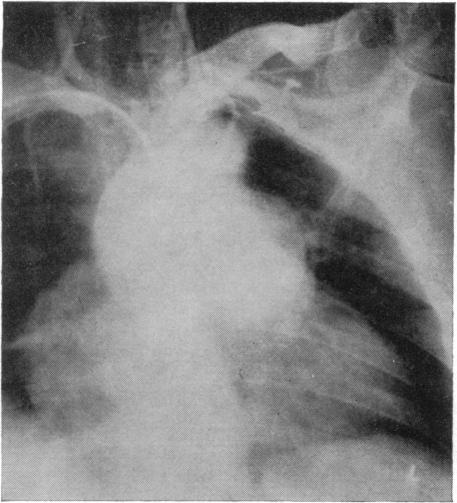

Closed injuries of the thoracic aorta.

Ann R Coll Surg Engl. 1972 Sep;51(3):137-56.